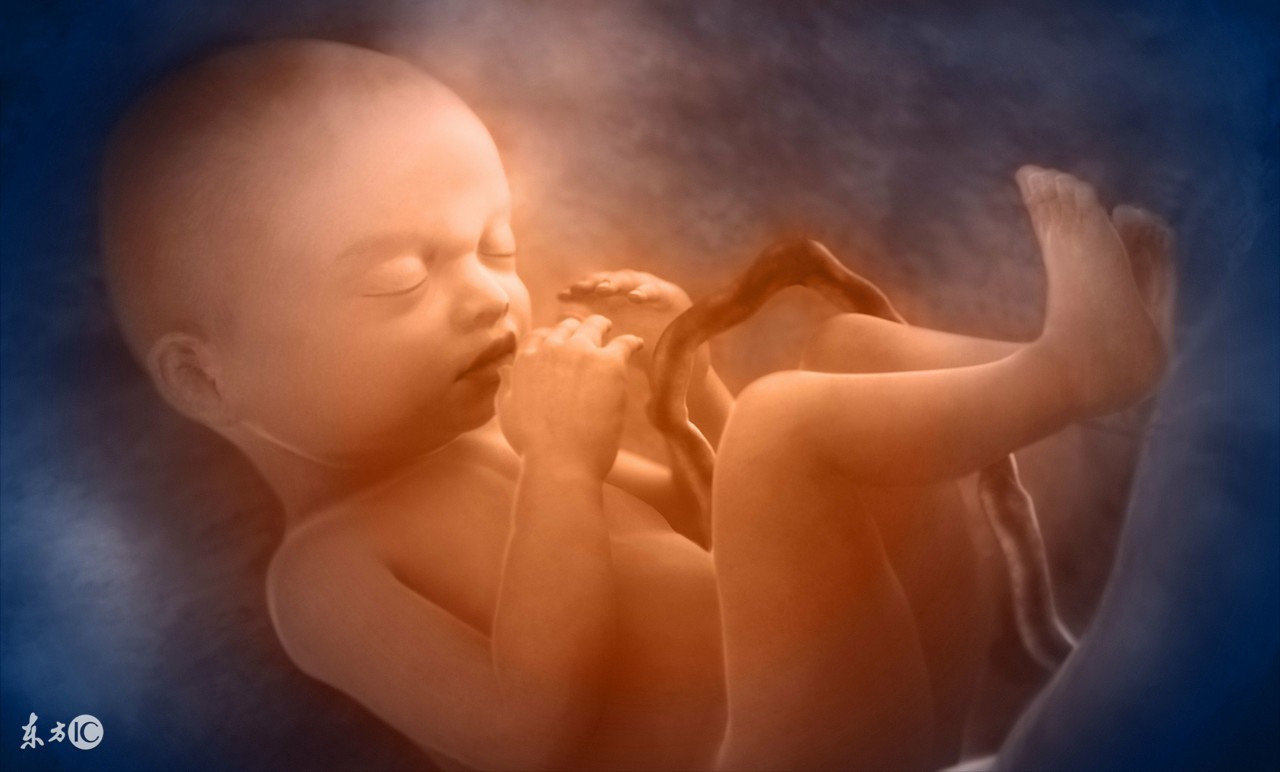

羊水能稳定子宫内温度,使之不至有剧烈变化,保护胎盘和脐带。

在胎儿的生长发育过程中,使胎儿能够在子宫内自如活动,因而,胎儿的肢体发育不至形成异常或畸形。

在妊娠期间,羊水能缓和腹部外来压力或冲击,保护胎儿使胎儿不至直接受到损伤。当胎宝宝在妈妈子宫里拳打脚踢的时候,也可以缓解妈妈的不适。